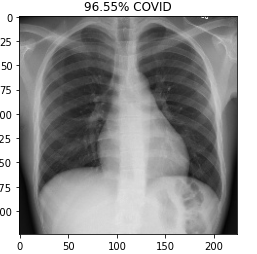

This is a Covid-19 virus detection application. Initially this application uses a machine learning model. The uses upload the Chest X-Ray or Brain scan Images to the user interface and the API take the input and proceed those input to ML model. The machine learning model process and analysis those inputs and generate output like a patient is a covid-19 +ve or covid-19 -ve. And finally the API take those inputs to the user interface. In this way this application basically works.